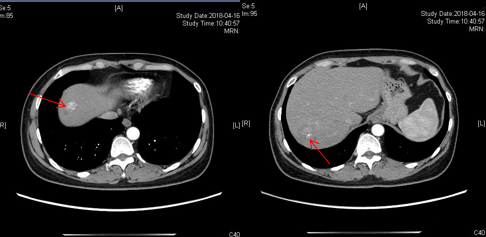

CT(2018-04-16):右肺中叶胸膜小结节;肝内多发混杂密度影,考虑为转移瘤;横结肠肝曲管壁局限性增厚 。